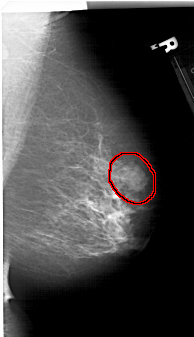

A_1411_1.RIGHT_MLO

RIGHT_MLO LINES 6391 PIXELS_PER_LINE 3676 BITS_PER_PIXEL 12 RESOLUTION 43.5 OVERLAY

FILE: A_1411_1.RIGHT_MLO.OVERLAY

TOTAL_ABNORMALITIES 1

ABNORMALITY 1

LESION_TYPE MASS SHAPE LOBULATED MARGINS MICROLOBULATED

ASSESSMENT 4

SUBTLETY 4

PATHOLOGY BENIGN

TOTAL_OUTLINES 1

BOUNDARY